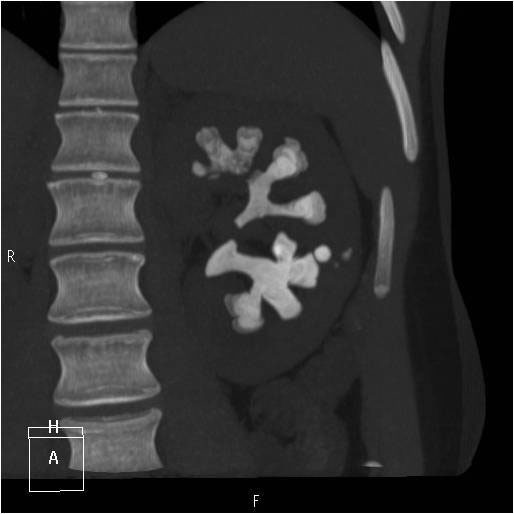

Raphaëlle Renard-Penna, La Revue du Praticien Uroscanner sans injection. Calcul coralliforme du rein gauche.